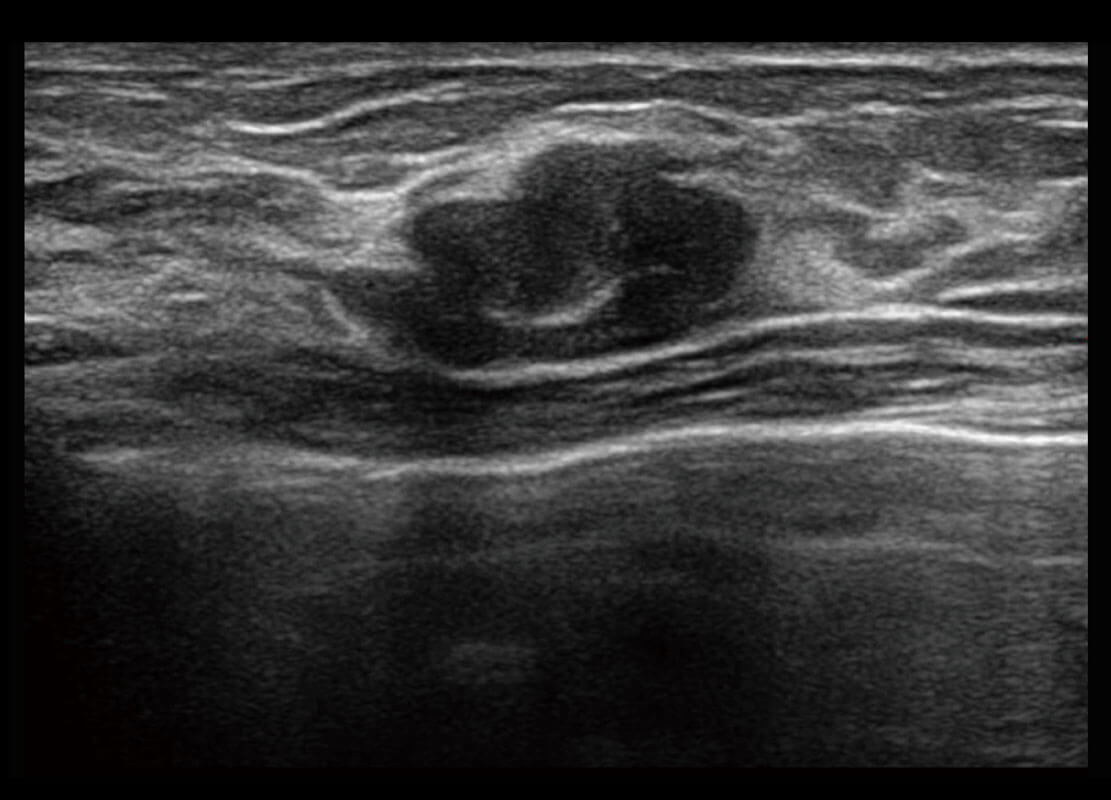

P60搭載寬頻帶線陣探頭、寬景成像、彈性成像技術(shù),為您提供乳腺應(yīng)用方案。P60支持高頻相控陣探頭、線陣探頭、腹部高頻探頭、腹部微凸探頭等,豐富的探頭群搭載敏感的彩色血流成像,適用于新生兒多種臟器檢測要求,滿足新生兒篩查需求。

乳腺導(dǎo)管癌